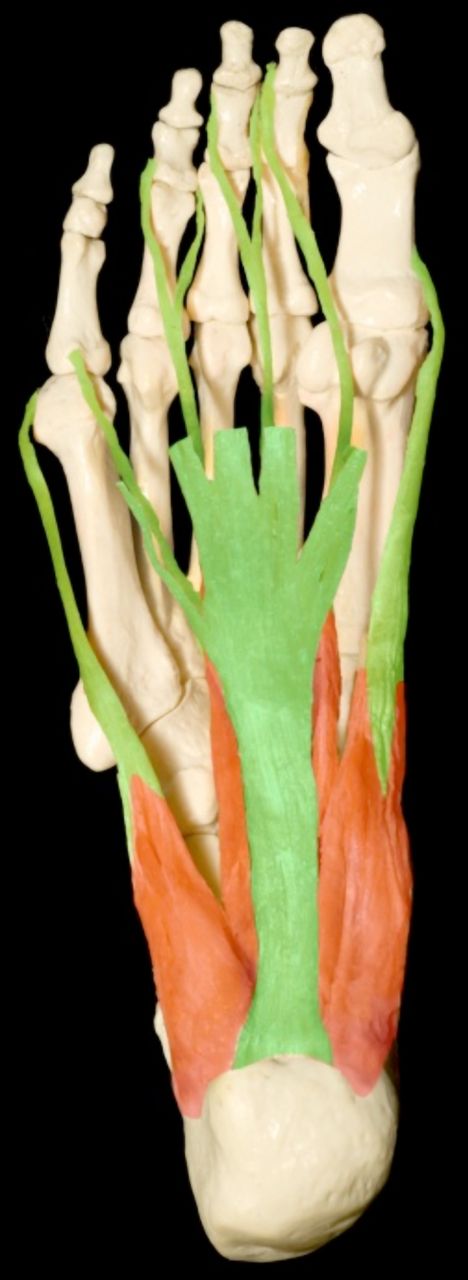

3.2 Plantar Fascia

The plantar fascia (or plantar aponeurosis) is a dense fascia (a strong layer of white fibrous) that runs nearly the entire length of the sole of foot (Figure 1). It begins posteriorly on the medial tubercle of the calcaneus and continues anteriorly to attach by digitations to the plantar plates and then, via the plates, to the proximal phalanx of each toe. From the beginning to the end of the stance phase of gait, tension on the plantar fascia increases, with maximum tension averaging 96% of body weight as force is transmitted from the Achilles tendon to the forefoot (Erdemir et al., 2004).

Towards the front of the foot, at the mid-metatarsal level, it divides into five sections, each extending into a toe and straddling the flexor tendons. Laterally, it is divided into three sections:

- Medial: The medial portion overlies the muscles to the hallux (big toe).

- Lateral: The lateral portion overlies muscles to the little toe.

- Central: Is designated as the plantar fascia. It is the most important structurally and functionally, and is attached at its origin to the medial calcaneus (heel bone).

The plantar fascia supports the longitudinal arch of the foot with a similar function as the bowstring of a bow or windlass (De Garceau et al., 2003). During walking, the plantar fascia functions mainly during ‘heel rise’ to ‘toe off.’ It stabilises the arch of the foot and allows flexion of the first metatarsal, enabling the first metatarsal to carry the majority of the body weight. It also provides shock absorption when the foot hits the ground. All three components of the plantar fascia arise from the plantar tubercle of the calcaneus. This segment of the plantar fascia is prone to degeneration or discrete tear.

The plantar fascia is a ligament in anatomical terms (Madden et al., 2010), because it attaches bone to bone (calcaneus to metatarsal heads, crossing other joints of the foot in its path, Figure 2) rather than a tendon (which attaches muscle to bone).

However, deep to the superficial structure of the plantar fascia is the flexor digitorum brevis muscle, with a tendon enthesis attachment to the calcaneus proximally. As stress shielding (failure of a stress deprived deep surface to heal because the superficial element bears most of the load) is potentially implicated in enthesopathy (Orchard et al., 2004), it is possible that proximal tendinopathy of the flexor digitorum brevis muscle is involved in the pathology of plantar fasciitis.